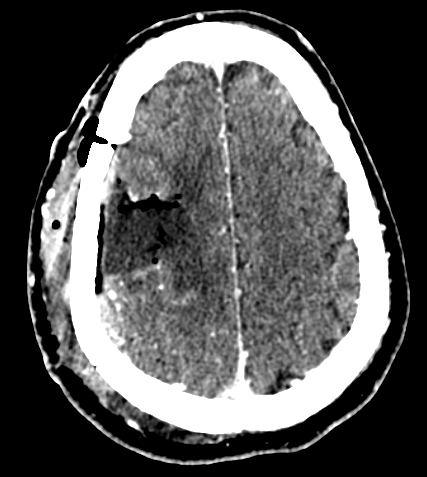

Resezione microchirurgica di tumore cerebrale (glioma alto grado cortico-sottocorticale) frontale dx